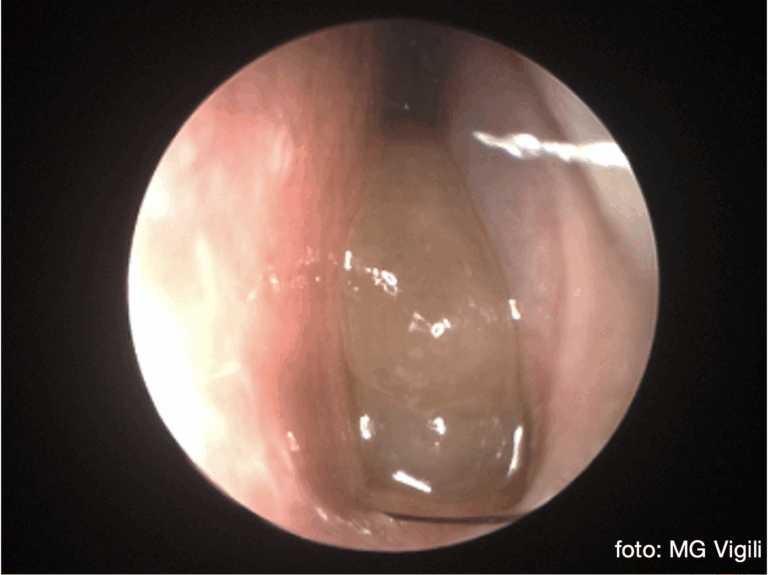

Claritromicina prolungata a basse dosi migliora i sintomi della sinusite cronica recalcitrante